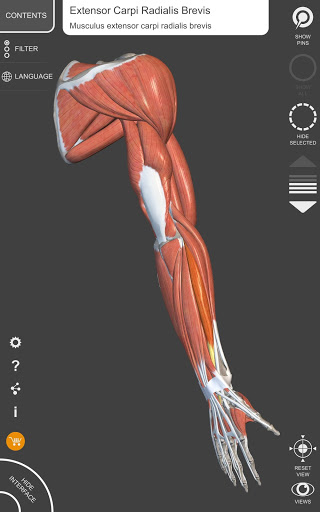

"Anatomy 3D Atlas" дозволяє легко та інтерактивно вивчати анатомію людини.

Завдяки простому та інтуїтивно зрозумілому інтерфейсу можна спостерігати кожну анатомічну структуру під будь-яким кутом.

Анатомічні 3D-моделі особливо деталізовані та мають текстури з роздільною здатністю до 4k.

АНАТОМІЧНІ 3D МОДЕЛІ

• Кістково-м’язова система

• Обертайте та збільшуйте кожну модель Тривимірний простір

• Візуалізація м’язів через рівні шарів від поверхневих донизу до найглибших